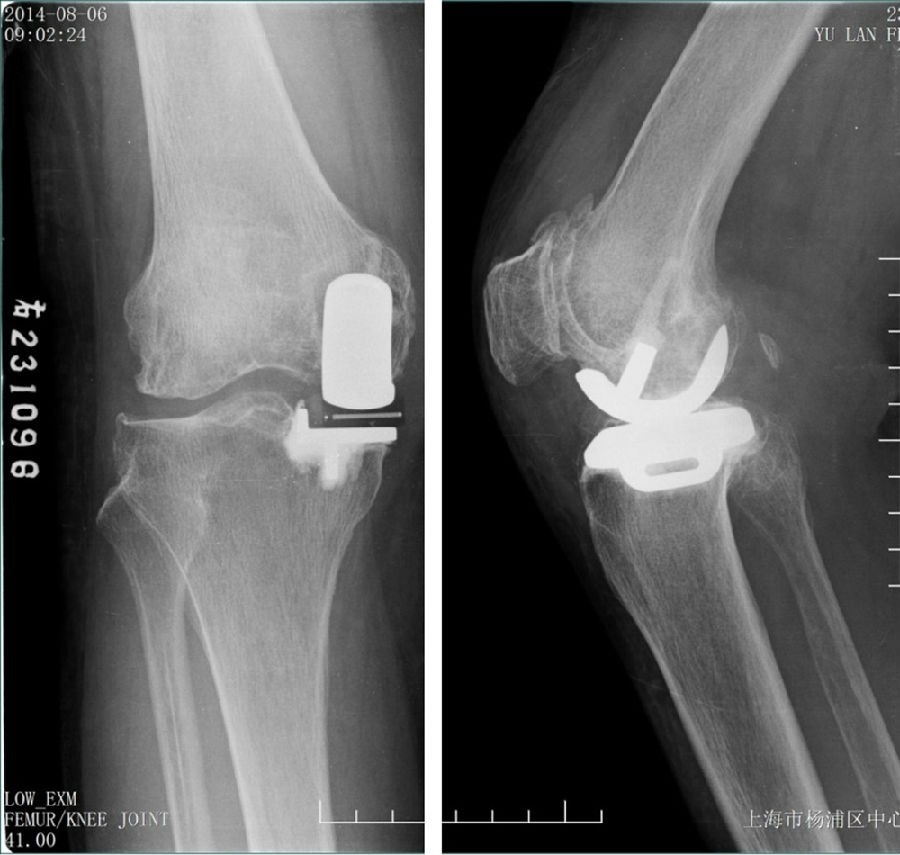

术后透视。A.正位B.侧位

术后1X-ray

术后1周下肢功能